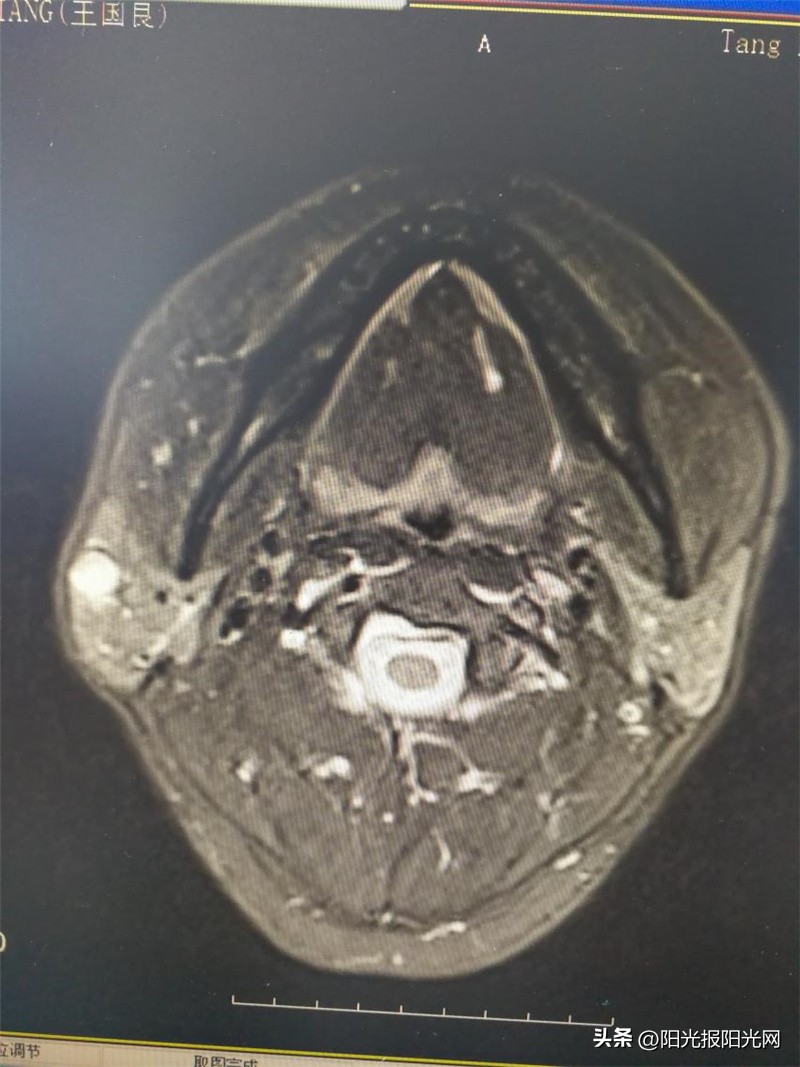

小陈(化名)医学影像